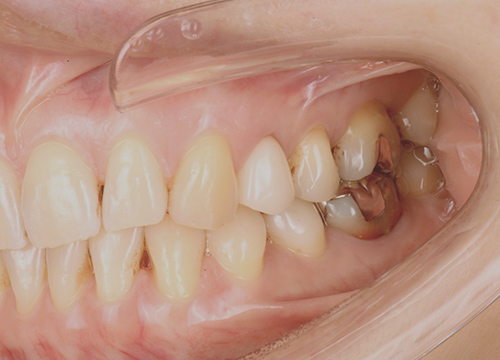

従来のインプラントでは悪くなった歯を抜歯し、骨や歯茎が回復した状態でインプラント手術をおこないます。

歯がなくなると骨は溶け、歯茎は凹んでしまい、前歯などの見た目に大きく関わる部位では、見た目をよくするためだけに、さらに歯茎を切って移植する大掛かりな手術をする必要があり、大きな痛みを伴ったり、治療期間が半年以上大幅にかかってしまう場合があります。

当院ではルートメンブレンテクニックを用いることで、骨や歯茎の減りを最小限におさえることができます。結果痛みも少なく、治療期間も3ヶ月程度となります。

抜歯後

治療後